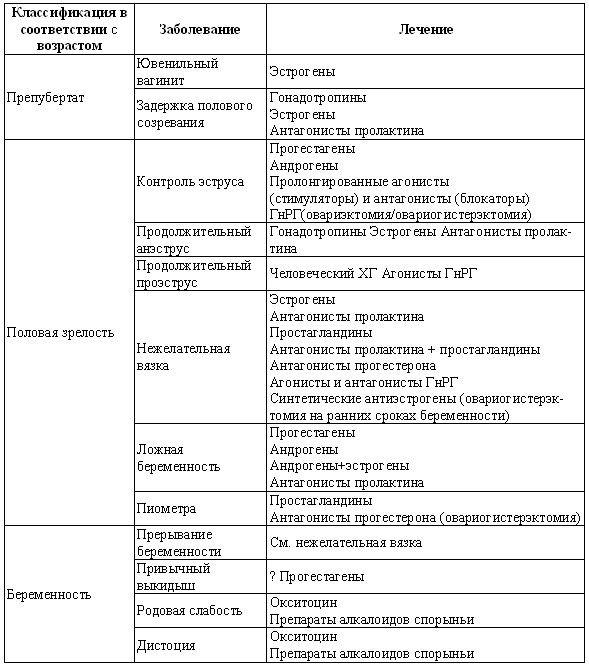

Бесплодием называют снижение способности к рождению потомства. С возрастом (после 6–7 лет) у сук и кошек эструс и беременность наблюдаются реже, и количество щенков/котят в помете сокращается. Причина бесплодия может заключаться в наличии репродуктивных проблем у самца и/или самки, нарушениях эстрального цикла или невозможности вязки. В основе этого лежат ошибки в содержании, поведенческие расстройства и нарушения развития, анатомические или функциональные изменения репродуктивного тракта, обусловленные инфекциями, неоплазией и ятрогенами.

Нарушения, характеризующиеся отсутствием эструса

Анэстрия может проявиться следующим образом: либо у самки в соответствующем возрасте не началась циклическая активность, либо увеличена продолжительность интер-про-эструса (т. е. более 12 месяцев для сук и более 20 дней для кошек), либо прекратилась циклическая активность. Патология обусловливается отсутствием явных признаков проэструса и эструса или структурными либо функциональными нарушениями в системе гипоталамус-гипофиз-яичники.